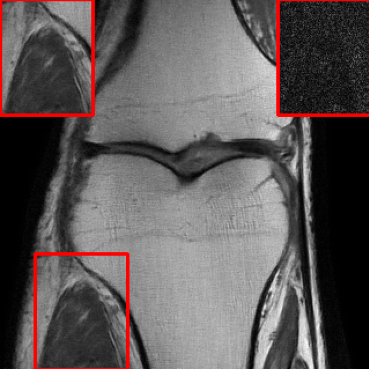

Figs. 4 and 5 show images reconstructed by different methods at 8x and 4x undersampling, respectively. The LONDN-MRI reconstructions (either iterative or oracle) show fewer artifacts, sharper features, and fewer errors than the global MoDL and initial aliased reconstructions. The iterative LONDN-MRI results are also quite close to the oracle result.

| Ground Truth | Global | LONDN-MRI | LONDN-MRI | Oracle |

| (1 iteration) | (2 iterations) | |||

![]() |

| PSNR = dB | PSNR = 32.78 dB | PSNR = 33.16 dB | PSNR = 33.25 dB | PSNR = 33.30 dB |

| Initial | DIP | SOUP-DIL | RAKI | LORAKI |

| PSNR = 21.23 dB | PSNR = 30.18 dB | PSNR = 30.66 dB | PSNR = 31.26 dB | PSNR = 31.67 dB |